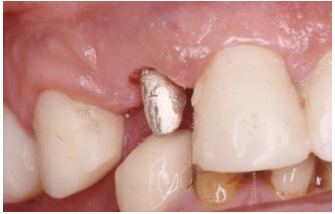

Revaluation, at six weeks, revealed that the inflammation of the periodontal tissues was significantly reduced and periodontal surgery for pocket elimination was not required. However teeth #35 and 12 necessitated surgical crown lengthening to preserve the biological width. Implant placement in #36 was designed with simultaneous crown exposure of #35 in order to shorten treatment plan time. An alternative procedure for crown lengthening was proposed for #12, thus an orthodontic extrusion was implemented. Orthodontic therapy required the separation of acrylic crown #12 from the splinted frontal bridge and the position of metal brackets in adjacent teeth (Figure 13). In less than three months, a significant extrusion of abutment #12 was completed (Figure 14 & 15). In order to stabilize the position of the extruded #12, the acrylic crown was splinted with adjacent acrylic ones. Surgical placement of implant #36 was combined with surgical exposure of #35. Three implants in positions #44, 45, 46 were also inserted.

Figure 14: Initial subgingival position of the abutment#12.

Figure 15: Final supra gingival position of #12 after orthodontic extrusion.